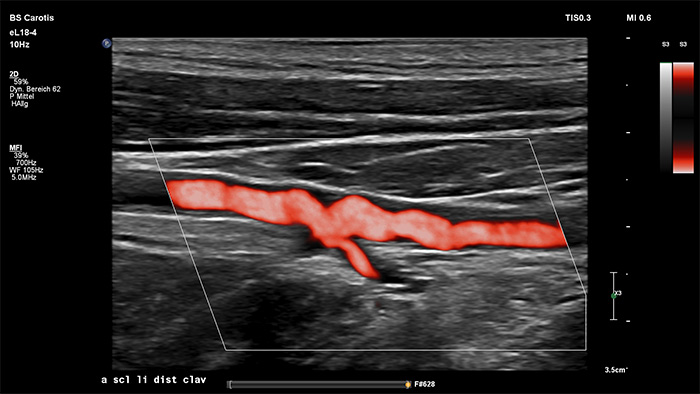

MicroFlow Imaging de Philips est conçu pour détecter les flux de très faible vitesse et de petit calibre au sein des tissus, avec une sensibilité remarquable, et améliore la résolution du flux lors d’explorations vasculaires. Grâce à sa haute résolution et à son faible nombre d’artefacts, les cliniciens peuvent visualiser et caractériser des perturbations subtiles du débit autour d’une plaque sténosée afin d’établir des diagnostics fiables.

L’interface utilisateur 3D/4D permet également de générer un moulage du vaisseau en utilisant les flux de données. L’image du vaisseau 3D permet la visualisation directe du flux pour une analyse plus approfondie des états sténosés ou tortueux. Atout majeur : la visualisation 3D/4D de haute qualité de l’anatomie vasculaire constitue un outil de communication idéal pour faciliter la prise de décision clinique parmi les professionnels de la santé et améliorer la consultation avec les patients afin de les aider à comprendre leur état.